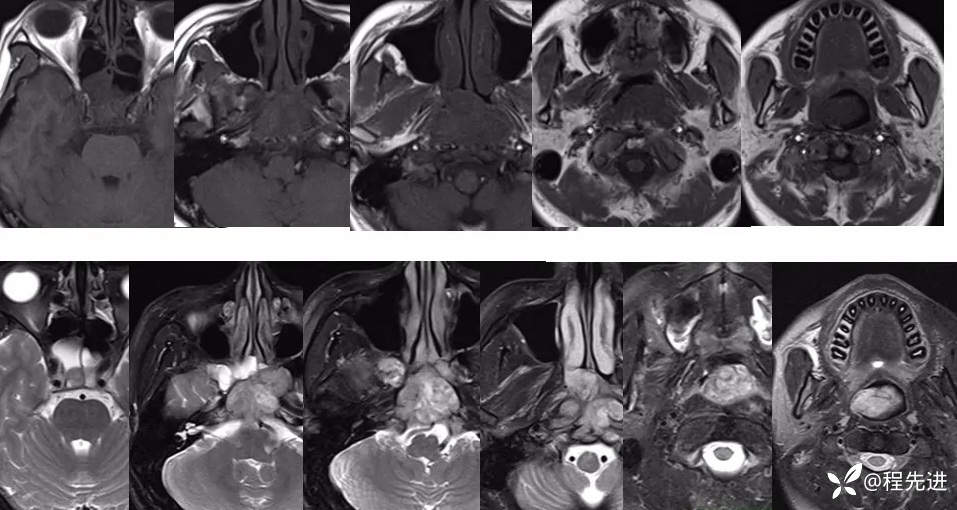

T1、T2: